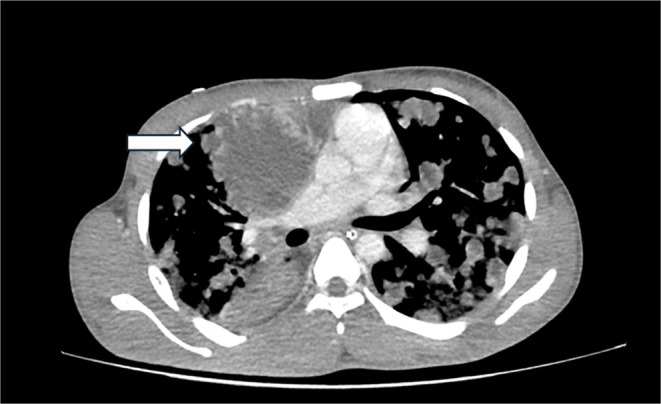

A previously healthy teenager presented with acute respiratory distress and constitutional symptoms. Imaging revealed a mediastinal mass with multiple pulmonary nodules, and markedly elevated β-HCG confirmed metastatic choriocarcinoma. Despite urgent chemotherapy, he succumbed within a week. This case underscores its rarity, diagnostic challenge, and dismal prognosis in tuberculosis-endemic regions.

Abstract Image